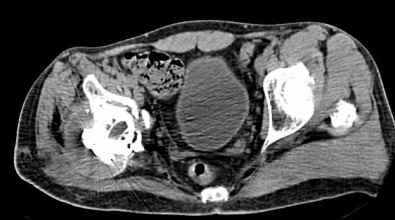

Мужчина, 45 лет. 6 мес. назад перенес тотальное эндопротезирование правого тазобедренного сустава по поводу ложного сустава шейки бедра.

Характер реконструкции вертлужной впадины не известен. Через 3 мес. после операции отметил щелчки и хруст при движениях в области эндопротеза. В анамнезе туберкулез легких. Сейчас, по заключению фтизиатра, в легких активного процесса нет. Местного воспаления нет.Предполагается нестабильность чашки в связи с бактериальным воспалением. Планируется удаление чашки и цемента, пластика дна измельченными аутотрансплантами и гидроксилапатитной керамикой, затем кольцо Мюллер, цементная чашка.

Мне кажется, что необходимо сначала выполнить пункцию, и принимать решение о тактике - исходя из результатов посева полученного пунктата.

И еще, в случае одномоментного реэндопротезирования здесь показана имплантация кольца Бур-Шнайдера (ИМХО)